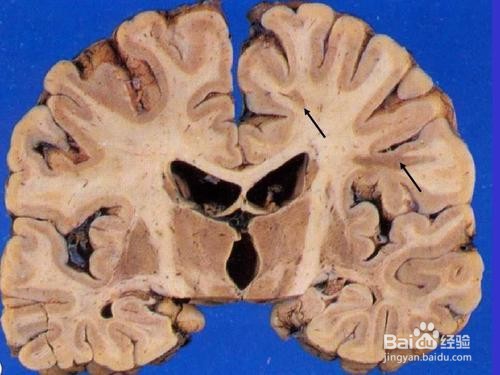

通过CT及MR(核磁共振)等影像学检查可发现双侧侧脑室及半卵圆中心点片状长T1 T2异常信号。脑室及脑池系统扩张,左侧颞部区见异常信号,脑中线结构局中。